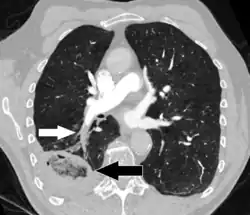

On CT scan, pulmonary emboli can be classified according to the level along the arterial tree.

Segmental and subsegmental pulmonary emboli on both sides

Pulmonary embolism (white arrow) that has been long-standing and has caused a lung infarction (black arrow) seen as a reverse halo sign